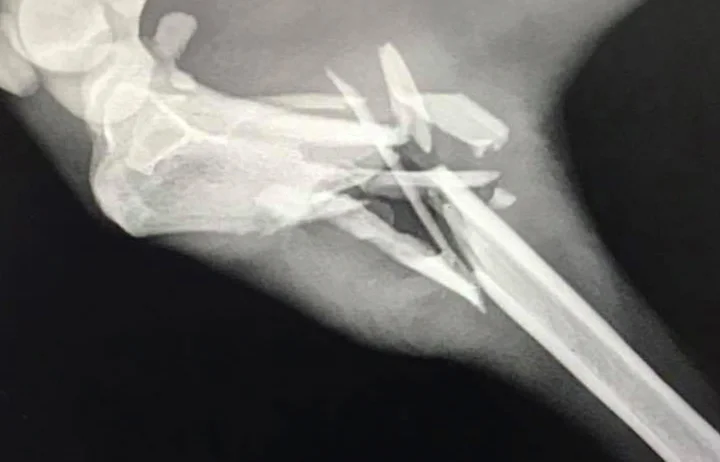

Sweet Eevee was found on the streets with an open fracture. The pain that this girl endured for over a week is unimaginable. The GDS vet amputated the leg as there was no way to save it. Eevee is a very friendly and sociable galga. Currently in a GdS foster home and settling really well, she is recuperating between the couch and a human bed finding them both very enjoyable.